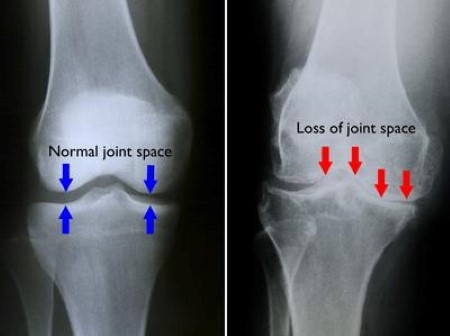

무릎 골관절염이란 사진의 오른쪽처럼 연골이 닳고 거칠어지면서 뼈 사이의 보호 공간이 줄어드는 것을 말한다. 결국 위아래 뼈가 마찰을 일으켜 통증이 나타나며, 퇴행성 질환으로 분류된다.